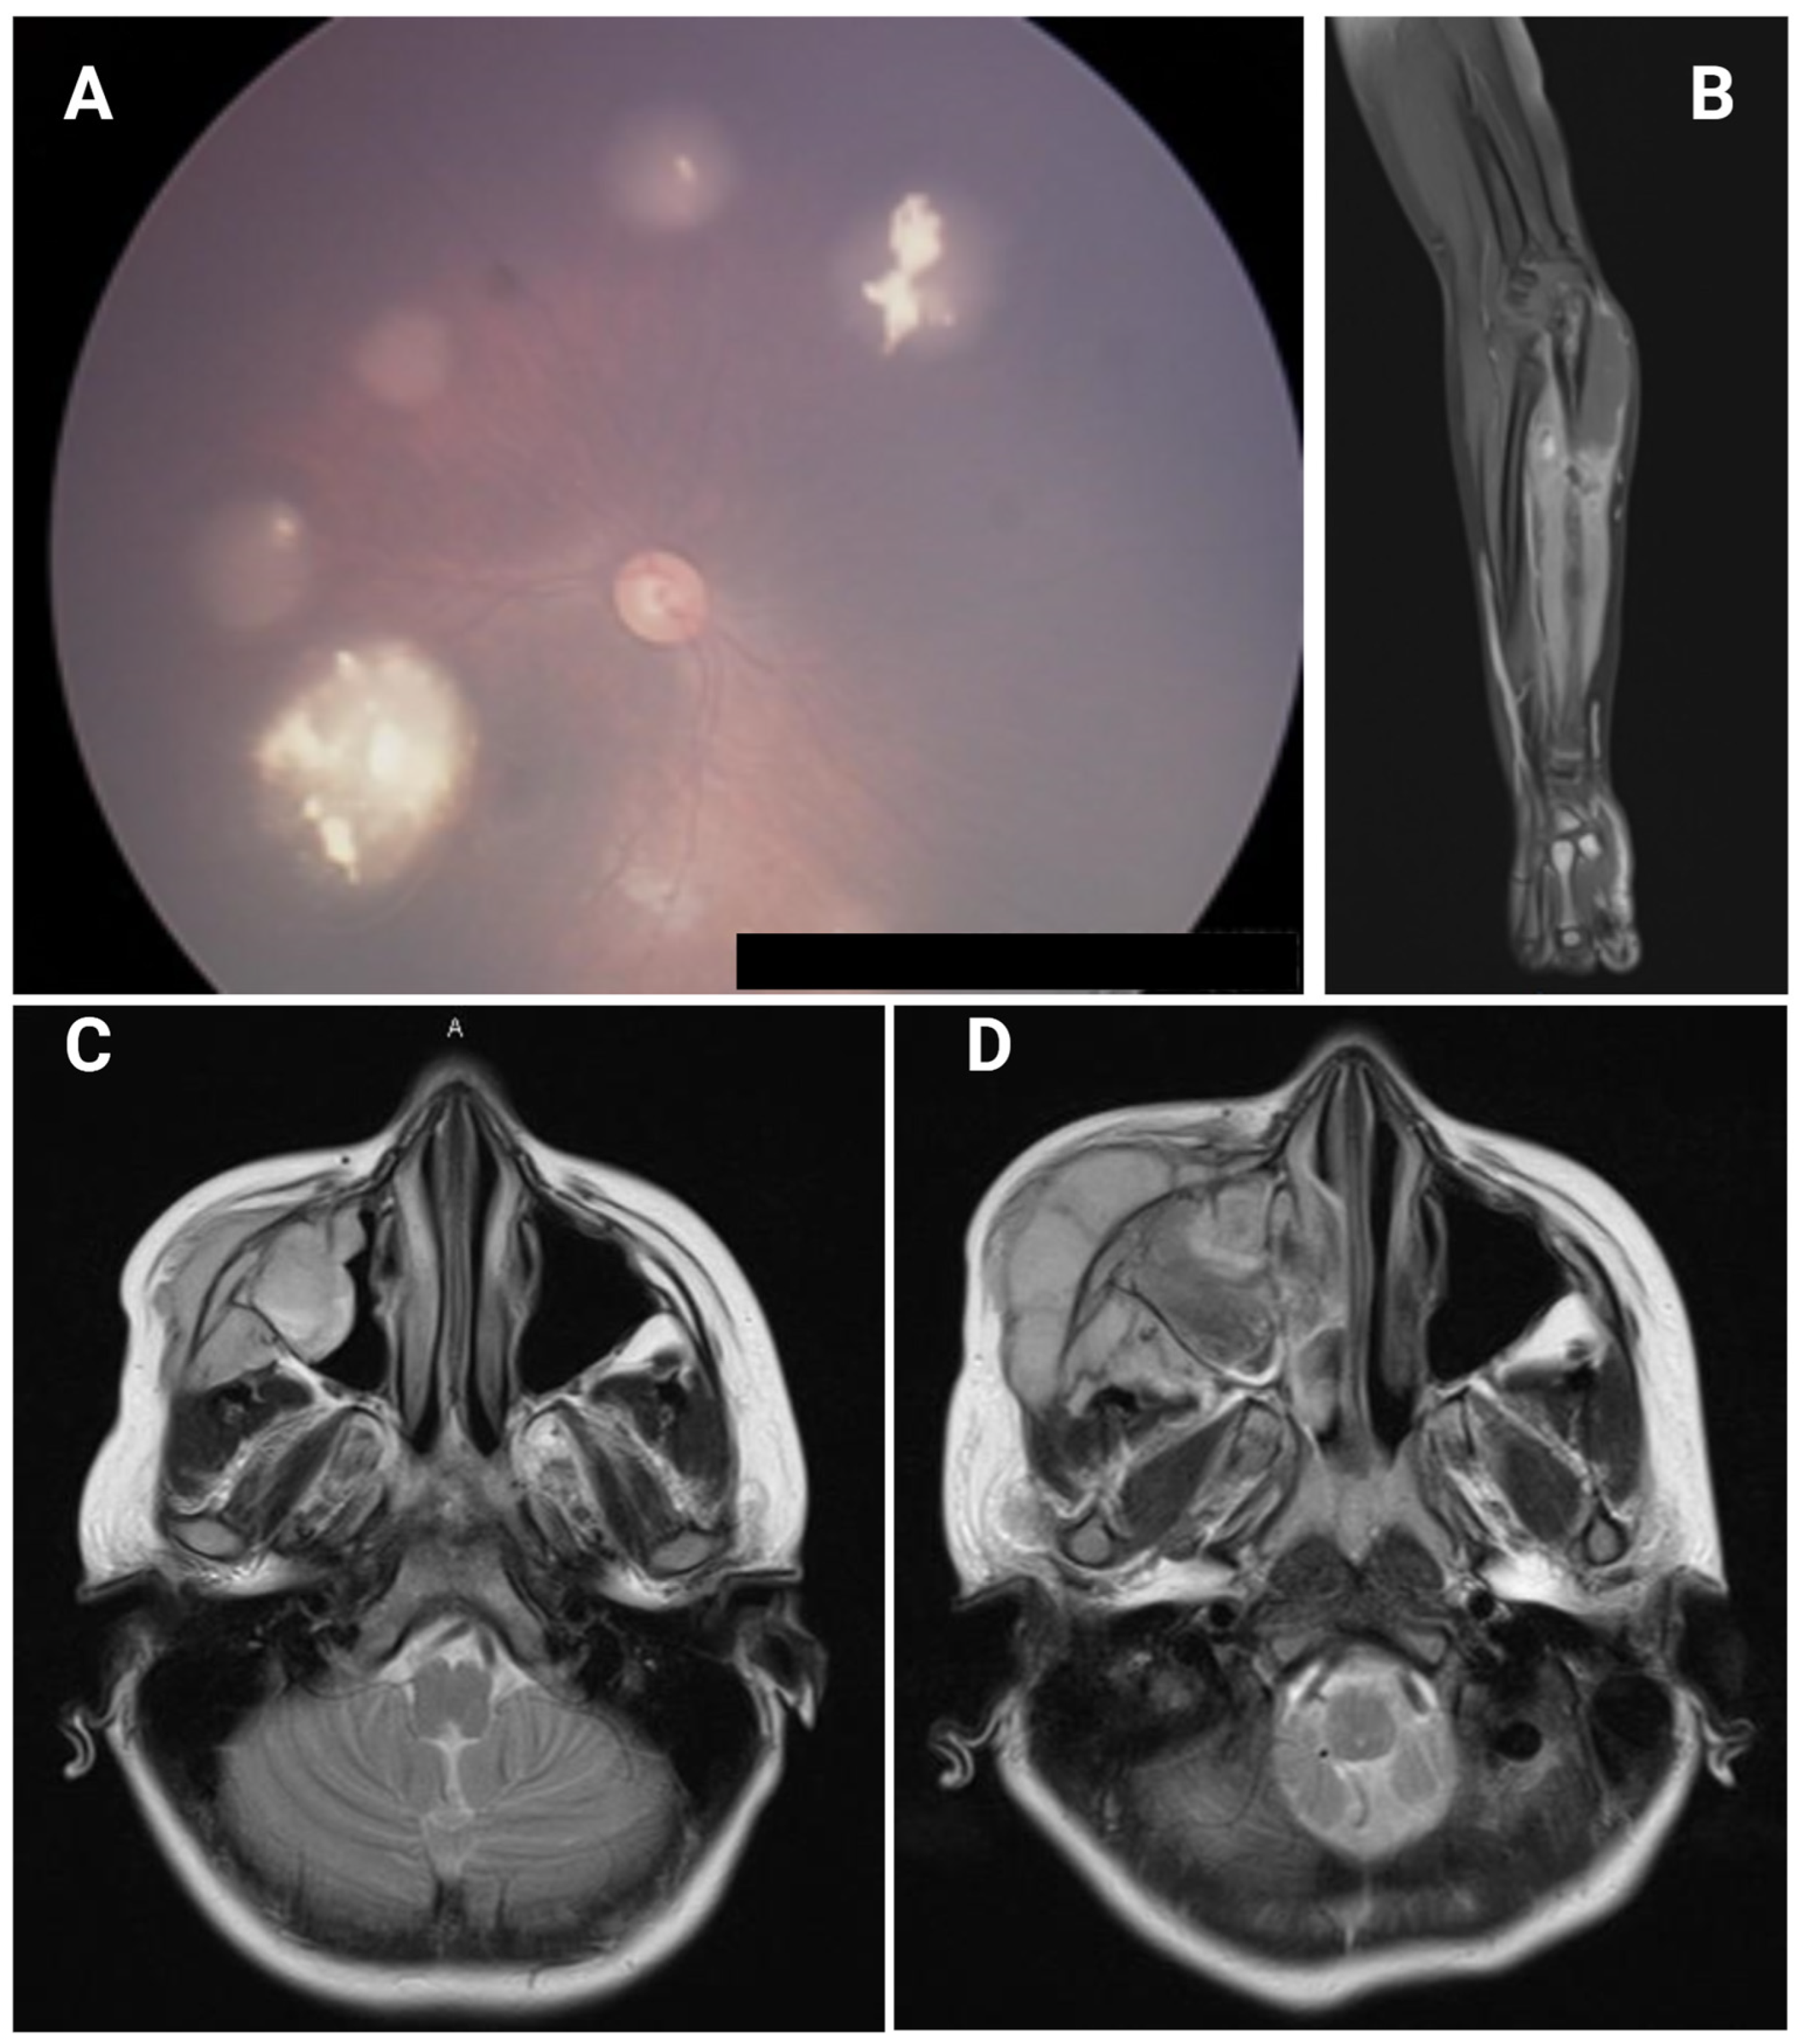

| F | 3 m | B | − | En, QT | 5 y | Sarcoma | Left ulna | 9 y | EWS | c.306T>A (p.Cys102*) | Present case |